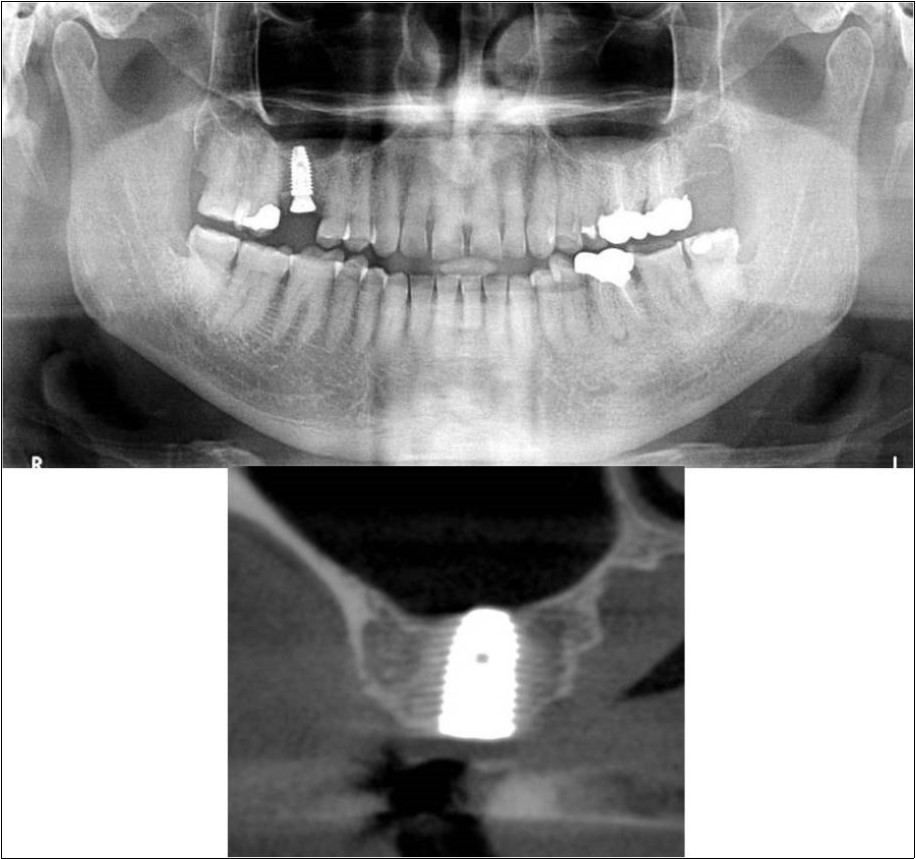

Treatment:

Patient underwent the procedure of indirect sinus elevation using sinus osteotomes in relation to 16 region. Calcium phosphosilicate putty was dispensed as the graft material through the crestal osteotomy site to maintain the elevated sinus membrane followed by placement of a dental implant measuring 5 x 10mm under local anaesthesia and strict aseptic protocols. The implant was allowed to osseo-integrate for a period of six months during which the patient was followed-up periodically and was assessed for peri-implantitis, crestal bone loss and mobility. At the end of 6 months, a repeat CBCT scan was advised to evaluate the increase in bone height. (Figure 11a,b, pre-treatment; Figure 12a,b, post-treatment)

Figure 11.(a,b) Pre-treatment OPG and cross section of CBCT showing residual alveolar bone height for Case No.3

Figure 12.(a,b) Post-treatment OPG and cross section of CBCT showing residual alveolar bone height for Case No.3;